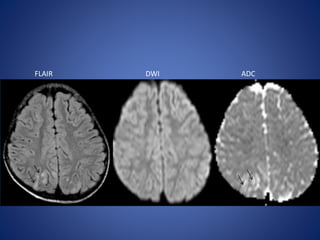

11 yrs male, with suspected Glomerulonephritis, presented with fever, anasarca, 2

episodes of GTCS

FLAIR DWI ADC

Other causes 11 yrsmale, with suspected Glomerulonephritis, presented with fever, anasarca, 2 episodes of GTCS